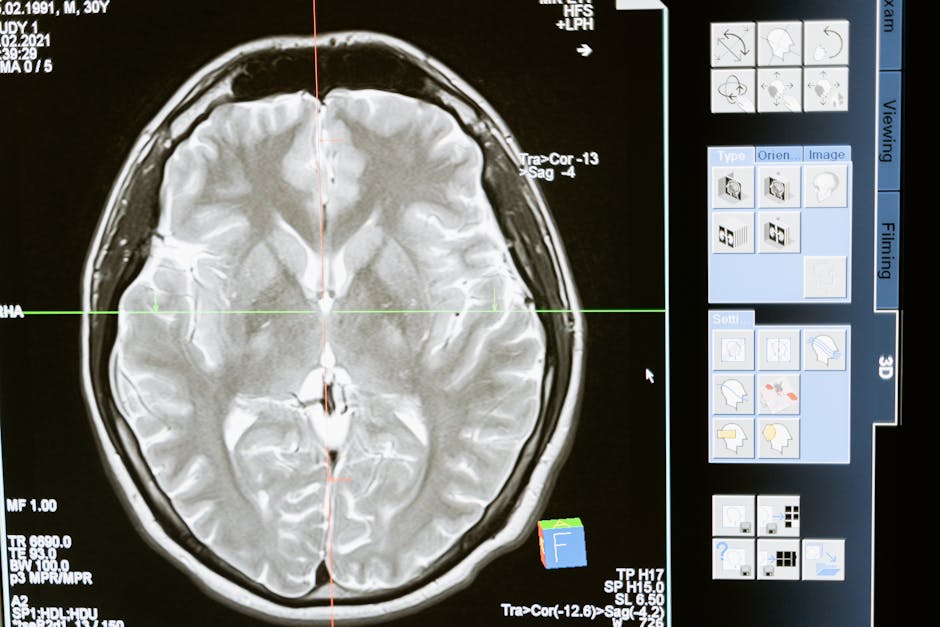

Dr Rhonda Patrick, znana badaczka w dziedzinie biologii starzenia, regularnie podkreśla znaczenie oliwy z oliwek extra virgin w temacie longevity. Andrew Huberman, neurobiolog ze Stanford University, w swoim podcaście wielokrotnie omawiał korzyści zdrowotne oliwy z oliwek, w tym wpływ na funkcje poznawcze i neuroprotekcję.